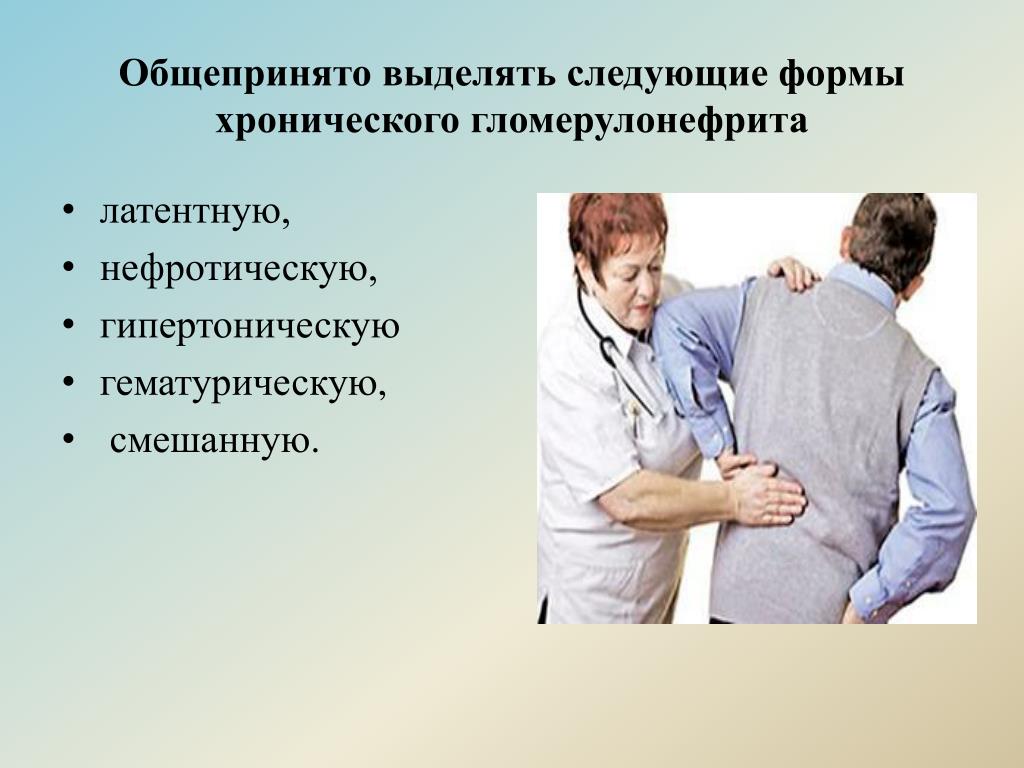

Симптомы подострого гломерулонефрита: фото и описание

Раздел: Визуальный дайджест